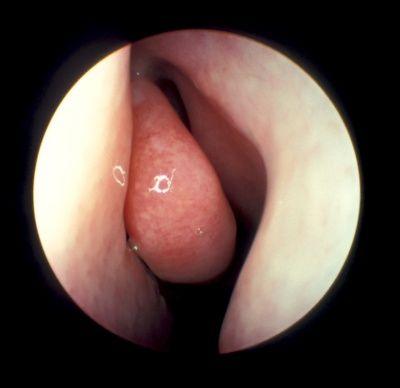

相关图片